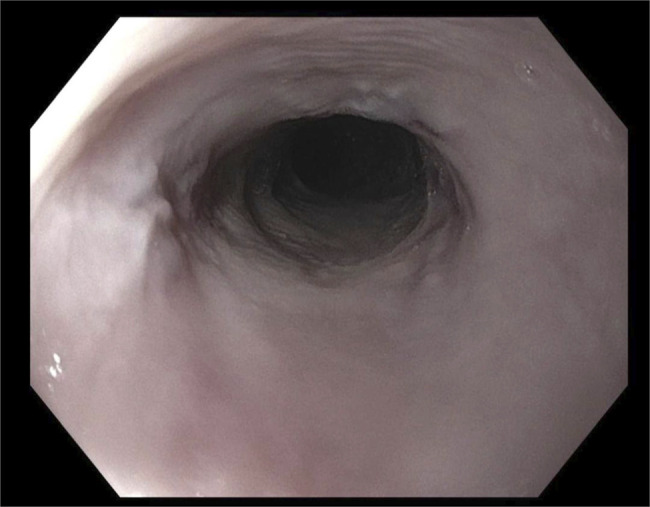

Abstract Image

Lichen planus (LP) is a chronic inflammatory disorder involving the skin and mucous membranes. Esophageal LP is often under-recognized and may present with or without other mucocutaneous sites of involvement. Its diagnosis is made challenging by its variable presentation and high rate of negative biopsies. Although some studies have suggested diagnostic criteria and severity grading, no formal guidelines exist. Diagnosis is made with a combination of clinical presentation, macroscopic findings on endoscopy, and histologic evidence. This case report highlights the challenges in the diagnosis of biopsy-negative esophageal LP and importance of timely diagnosis and initiation of appropriate medical therapy.